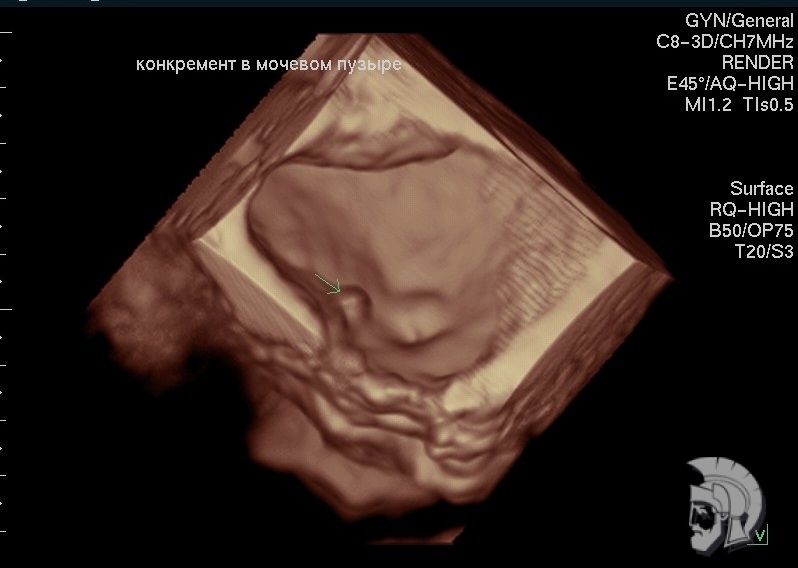

3D-фото мочевого пузыря.

«Камень» 4.5 мм в диаметре в мочевом пузыре мужчины 50 лет. «Камень» указан стрелкой |